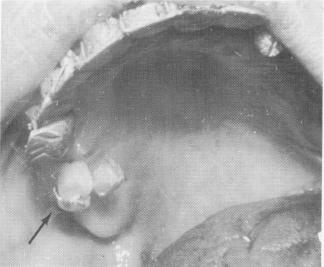

trapped inside the acrylic core. This weakens it, and it may crack or the pins may loosen inside the core. The core should be built by starting at the most gingival portion of the pins and gradually building up in an occlusal direction until the ends of the pins, which were previously notched with a fissure bur for added retention, are completely encapsulated with the acrylic core. In this way no bubbles should be included in the core. This is the most successful method known so far (Fig. 14-31).

Fig. 14-31. An aluminum shell previously filled with cold cure acrylic and placed over the ends of the pins was disked open after the acrylic hardened. However, the core (arrow) fabricated in this method might contain air bubbles. There-fore it is necessary to always build the core with the brush-on technique.